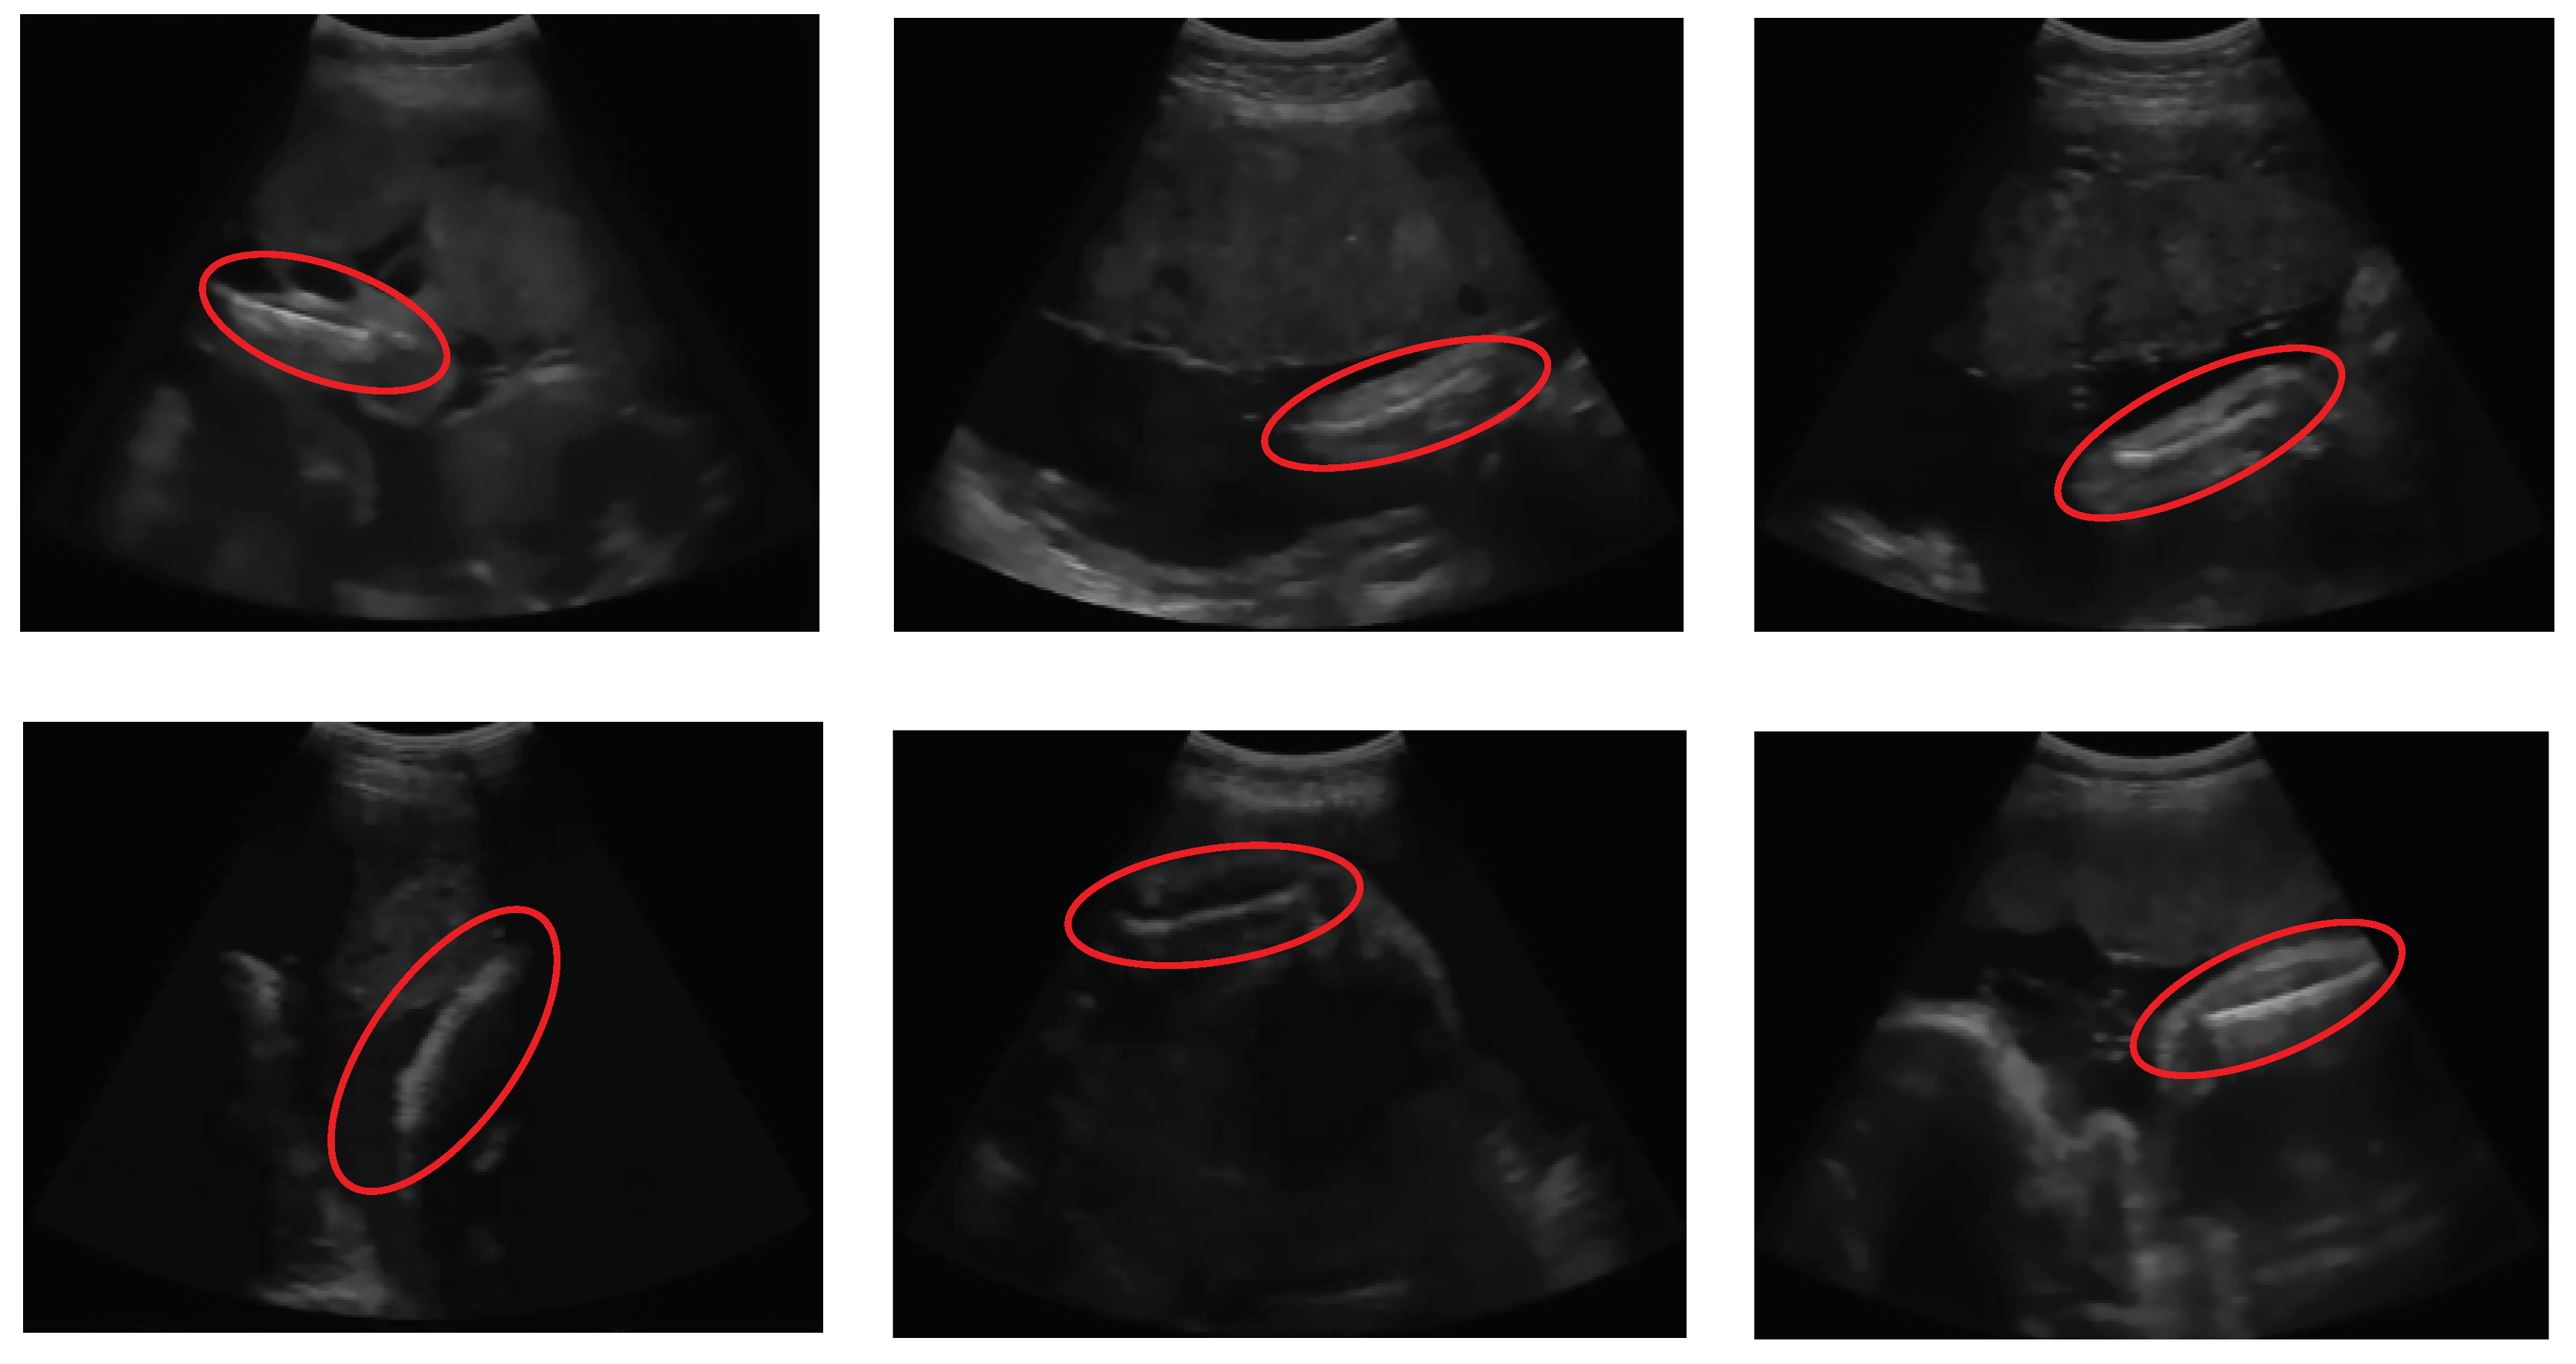

Some femur detection failures of other methods are shown in Figure 22. Failure of the entropy method occurs because the threshold result is only a few pixels and is in the upper boundary area of the image. Thus, the point is detected as the starting point of the segmentation of the femur object, as shown in Figure 22(a). The error of the Otsu multilevel method, as shown in Figure 22(b), is due to the broader thresholding results from the top to the lower end. Therefore, at the object selection stage, the area was discarded because the femur was not indicated, and the object of the femur was a smaller object. In statistical-based methods, femur errors occur at a gestational age of approximately 15 weeks, when the size of the femur is small, and an ultrasound probe still exposes the foetal sac. The outer area of the sac had an intensity value higher than that of the femur bone, so that the region was recognised as a femur object, as shown in Figure 22(c).

Figure 22. Failures result of (a) entropy-based method, (b) multilevel Otsu method, (c) statistical-based method, where the dash line is the ground truth, and the straight line is a detected FL.